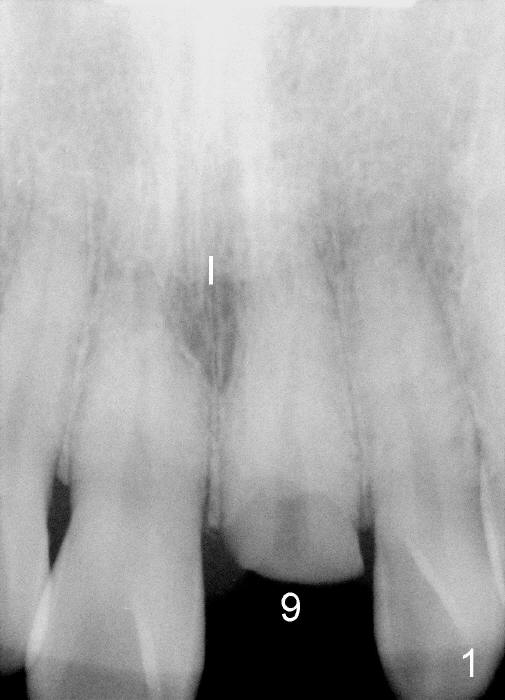

The upper right central incisor (Fig.1: #9) fractures subgingivally due to trauma for a 40-year-old man.  The incisive canal is large (I) and close to the root of the central incisor.  After extraction, the osteotomy (Fig.3b, 4: O) is made with 2 mm pilot drill (Fig.2: D) on the lingual wall (Fig.3a: L) of the socket (Fig.3a: S).  To push the incisive canal mesially, the osteotomy is enlarged by 3.5x21 mm and 4x21 mm tapered osteotomes (Fig.5,6: O).  Due to the lingual slope (Fig.7a arrow), the osteotome (blue outline) starts to deviate bucally.  To reduce this tendency, the coronal portion of the lingual slope is removed (Fig.7b: yellow circle).  The final implant (4.5x20 mm) is able to be placed as lingually as possible (Fig.7c, 8).